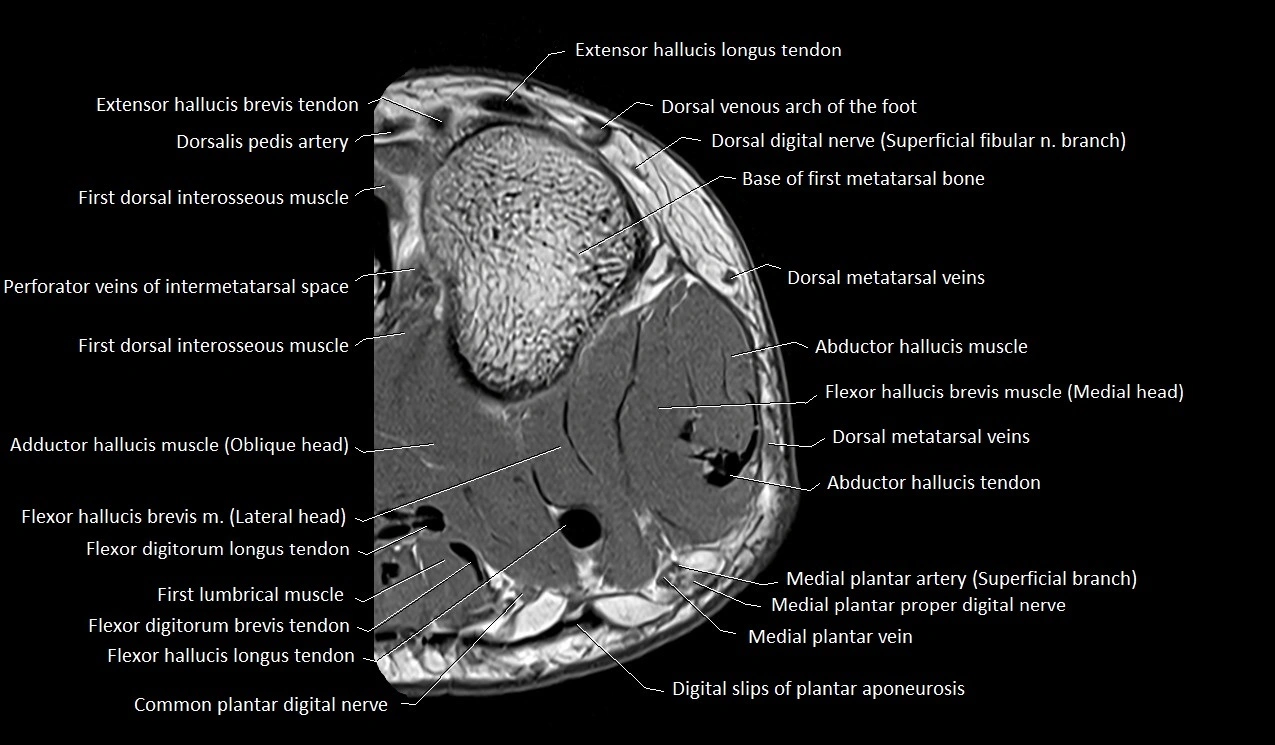

MRI image

image